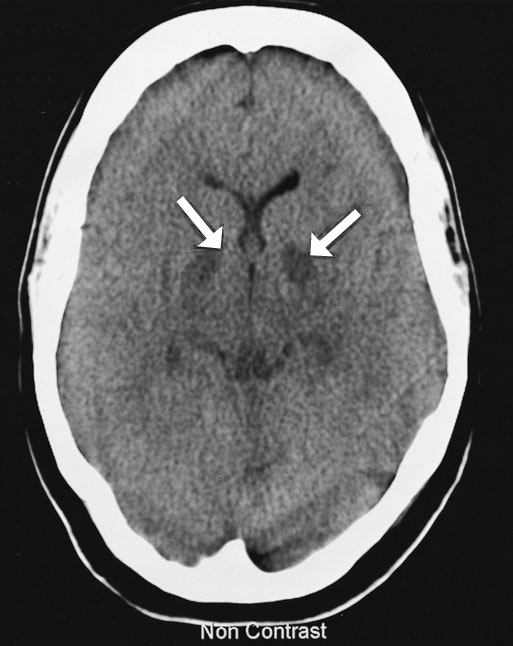

The next day, cerebral computed tomography (CT) scan showed changes in the basal ganglia and mild generalised cerebral swelling consistent with severe hypoxia (Box 2A). A CT scan of her abdomen showed generalised changes in the bowel wall and mesentery consistent with bowel necrosis (Box 2B). Surgical intervention was considered to offer little in view of the severe neurological damage and multiorgan failure. Following extensive discussion with family members, inotropic support was withdrawn and she died soon afterwards.